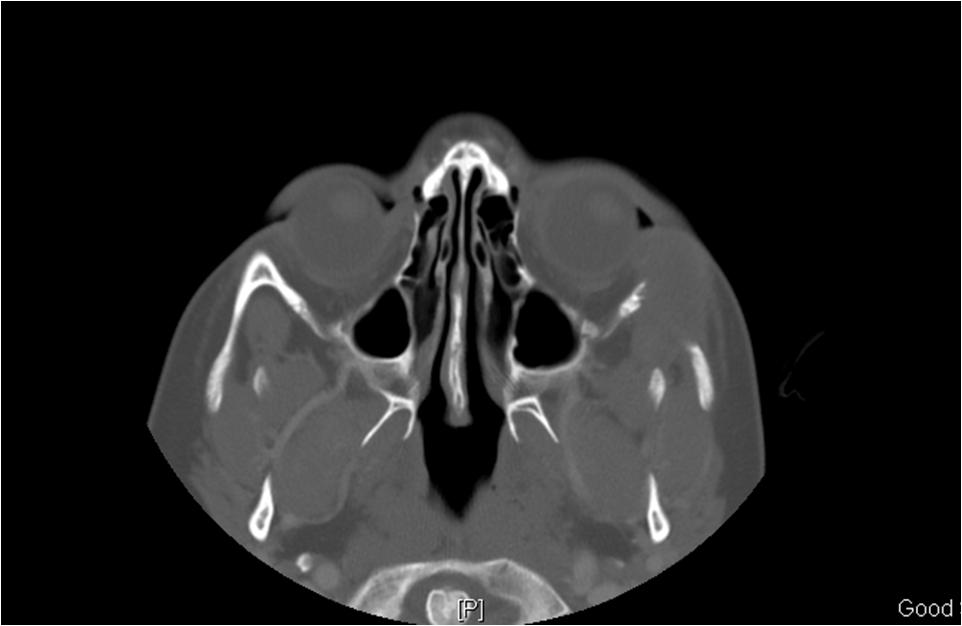

On imaging presentation is variable but it typically presents as a lytic defect most commonly seen in superotemporal orbit or sphenoid wing. The LCH disorders have a predilection for hematopoietically active bone marrow so this is why it is seen in the supero-temporal orbit quite commonly. LCH lesions enhanced only minimally with contrast on CT. On T1-weighted MRI images typically showed soft tissue masses with signal intensity similar to muscle, and enhances well with fat-suppression and gadolinunium. [10] The histological diagnosis of LCH lesions is based on staining for S-100 protein and CD1a antigen or finding Birbeck granules (shaped like tennis racquets) on electron microscopy.[11][12]

As a general clinical pearl, if you do see a lytic bony changes on CT in a child you should strongly consider this disease as a possible diagnosis. However, while imaging findings are fairly uniform in LCH, they are not pathognomonic, and other serious conditions in the same age group can have similar manifestations such Neuroblastoma, Ewing sarcoma, and Wilms tumor (all of which can each metastasize to the pediatric orbit). [15]